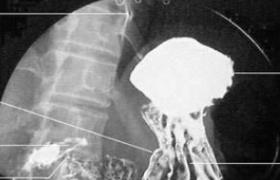

食管造影

252

上消化道造影

243